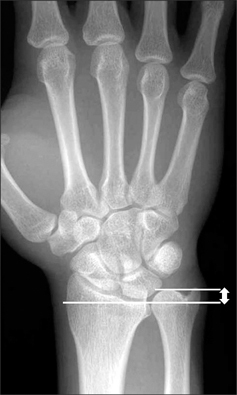

How is the load distribution in the wrist affected by ulnar variance?

What conditions are associated with the pathological finding of this XR? What would you expect to find on physical exam?

Ulnar Positive Variance

What conditions are associated with the pathological finding of this XR?

Ulnar Negative Variance

How does position of the forearm affect ulnar variance?

A pronated grip view is the best to determine your ulnar varience